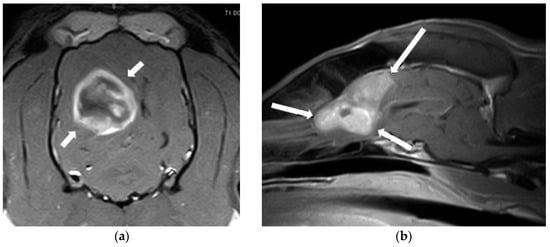

2.1. Intracranial Neoplasia